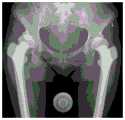

图3-4是根据本申请实施例提供的一种确定临床中的实际截骨线位置的示意图;3-4 are schematic diagrams of determining the actual position of the osteotomy line in the clinic according to an embodiment of the present application;

具体的,“根据股骨柄假体的旋转中心和在髋关节的X线图像识别过程中确定的髋臼杯的旋转中心确定截骨线位置”为通过移动股骨柄假体,将股骨柄假体的旋转中心与之前计算的髋臼杯旋转中心位置重合,得到股骨柄假体实际位置。沿股骨柄假体的涂层位置可确定临床中的实际截骨线位置,如图3-4所示。图3为移动股骨柄假体到预定位置,使股骨柄假体的旋转中心与之前计算的髋臼杯旋转中心位置重合,图4为根据股骨柄假体的外形确定截骨线位置。Specifically, “determine the position of the osteotomy line according to the rotation center of the femoral stem prosthesis and the rotation center of the acetabular cup determined during the X-ray image recognition of the hip joint” is to move the femoral stem prosthesis to move the femoral stem prosthesis The center of rotation of the acetabular cup coincides with the previously calculated center of rotation of the acetabular cup to obtain the actual position of the femoral stem prosthesis. The location of the coating along the femoral stem component can determine the actual position of the osteotomy line in clinical practice, as shown in Figure 3-4. Figure 3 shows moving the femoral stem prosthesis to a predetermined position so that the rotation center of the femoral stem prosthesis coincides with the previously calculated acetabular cup rotation center position, and Figure 4 shows the position of the osteotomy line determined according to the shape of the femoral stem prosthesis.